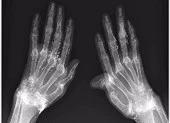

(PLO)- Các bác sĩ ở một bệnh viện Hàn Quốc đã rất kinh ngạc khi xem phim chụp X-quang bàn tay của một nữ bệnh nhân 58 tuổi vì thấy những cụm sợi màu trắng sáng lấp lánh quanh khớp cổ tay, ngón tay.